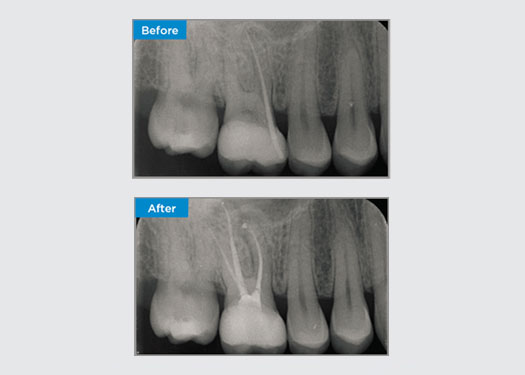

На прием к врачу обратился пациент с бессимптомным апикальным пародонтитом на зубе 34. На предоперационной рентгенограмме был отмечен зуб 34 с двумя видимыми корнями. Однако CBCT-сканирование подтвердило наличие трехкорневого премоляра, а каналы разделились на три в средней части корня. Для этого деликатного зуба очень важен тщательный подбор файла.

Доктор Джек Лин, Эндодонтист, Сидней, Новый Южный Уэльс, Австралия

В этой ситуации необходимо сохранить структуру зуба/корня, чтобы снизить риск формирования уступа, смещения, зиппинга, перфорации и перелома корня. Выбор случая, диагностика и предварительное планирование лечения очень важны. Выбор эндодонтического файла, обеспечивающего гибкость, эффективность и соблюдение естественной анатомии корня, имеют решающее значение.